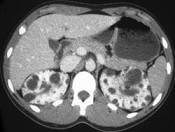

- 单项选择题男性,40岁, 因腰痛血尿就诊,B超检查发现肾脏增大, CT表现如图所示,追问病史发现家族中有类似疾病, 最可能考虑为 ( )

A、多囊肾

B、肾积水

C、多发性肾囊肿

D、肾肿瘤

E、肾结核